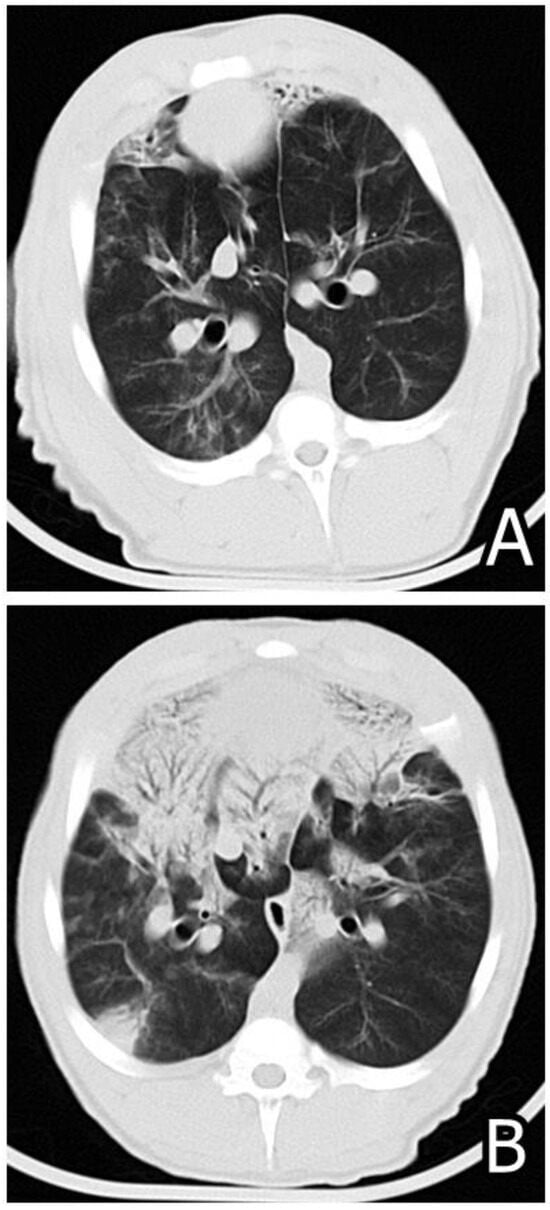

- Pósa, R.; Donkó, T.; Bogner, P.; Kovács, M.; Repa, I.; Magyar, T. Interaction of Bordetella bronchiseptica, Pasteurella multocida and fumonisin B1 in the porcine respiratory tract followed up by computed tomography. Can. J. Vet. Res. 2011, 75, 176–183. [Google Scholar] [PubMed]

- Pósa, R.; Magyar, T.; Stoev, S.D.; Glávits, R.; Donkó, T.; Repa, I.; Kovács, M. Use of Computed Tomography and Histopathologic Review for Lung Lesions Produced by the Interaction between Mycoplasma hyopneumoniae and Fumonisin Mycotoxins in Pigs. Vet. Pathol. 2013, 50, 971–979. [Google Scholar] [CrossRef] [PubMed]

- Pósa, R.; Stoev, S.D.; Kovács, M.; Donkó, T.; Repa, I.; Magyar, T. A comparative pathological finding in pigs exposed to fumonisin B1 and/or Mycoplasma hyopneumoniae. Toxicol. Ind. Health 2016, 32, 998–1012. [Google Scholar] [CrossRef] [PubMed]